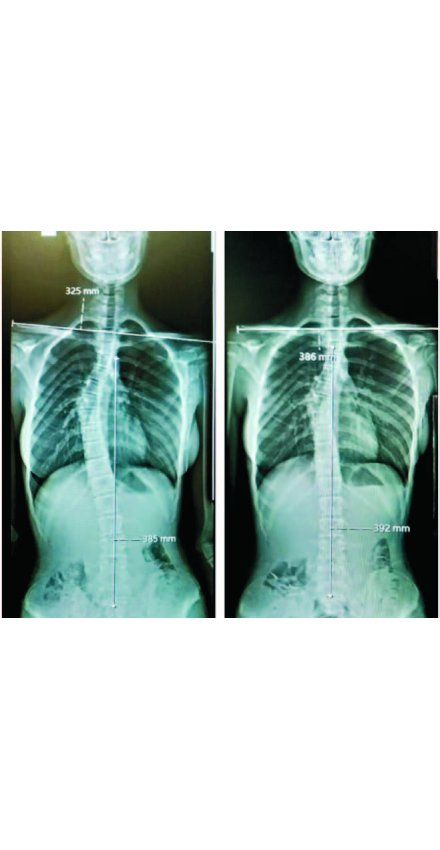

Elif Akıncı Pozitif Yaşam Merkezi’nin sahibi, başarılı fizyoterapist Elif Akıncı, özellikle gelişme çağındaki çocuklarda daha sık görülen omurga rahatsızlıkları konusunda uyguladığı başarılı yöntemlerle adını sadece ilimizde değil Türkiye genelinde duyurmayı başardı. Geliştirdiği Rubatonik Pilates yöntemiyle Almanya, İngiltere ve Barcelona menşeli spesifik omurga egzersizlerini 18 yıllık tecrübesiyle harmanlayarak kişiye özel egzersiz programları oluşturan başarılı fizyoterapist Elif Akıncı, son olarak skolyoz rahatsızlığıyla mücadele eden Zeynep Beyza Gündoğdu’nun doktoru tarafından 32° olarak ölçülen skolyoz açısını 3 ayda 20°’ye düşürmesini sağlayarak ağrılarını dindirerek rahat bir nefes almasını sağladı.

Skolyozu olduğunu tesadüf eseri öğrenen ve soluğu Elif Akıncı Pozitif Yaşam Merkezi’nde alan 14 yaşındaki Zeynep Beyza Gündoğdu, 3 ay boyunca uygulanan egzersiz programı sonrasında skolyozunun 12 derece gerilediğini söyledi. Gündoğdu, yaşadığı süreci şöyle anlattı: